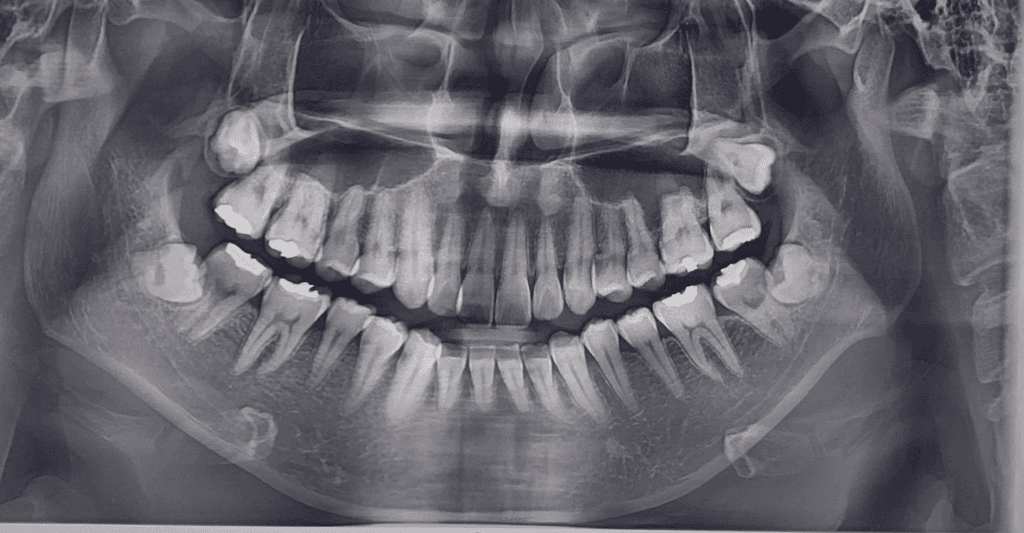

엑스레이 사진상 충치가 있는지 궁금합니다

엑스레이 사진에 충치가 있는 지 궁금합니다.

이렇다 한 통증은 없습니다만

일반인이라 충치 보는 법을 알아도

잘 색별해낼 수가 없더라구요

궁금합니다.

• 1번 째 사진

엑스레이 상으로 치아 사이에 충치가 의심되는 부분이 몇군데 잇기는 하지만, 정확한건 더 작은 엑스레이 사진을 찍어봐야 알것같습니다.

엑스레이상이 큰 충치는 없어보입니다.

이전에 충전한 재료 주변에 방사선투과성이 보이기는 하는데 이부위는 육안으로 직접 확인을 해야 알수 있을것 같아요.

엑스레이상으로는 충치를 확인하기는 어려우며, 육안으로는 표면에 검은색으로 썩은부위가 나타납니다. 하지만 육안으로 충치가 구분이 어려울수 있기에 보다 정확한 진단을 위해 치과진료를 받길 권합니다